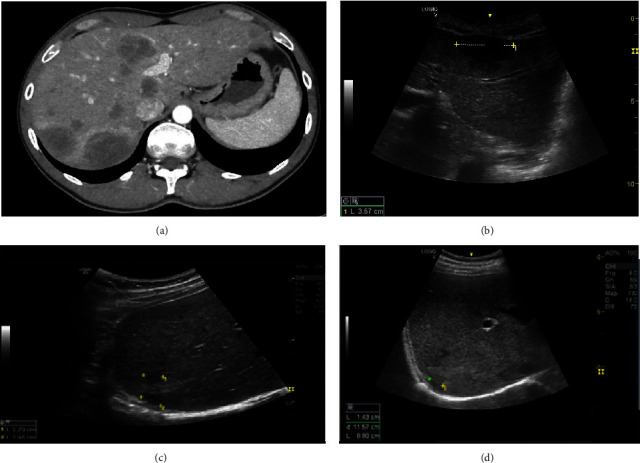

Syphilis is a sexually transmitted infection caused by Treponema pallidum. It progresses in phases and undiagnosed disease can cause considerable morbidity. Tertiary syphilis causes the formation of gummas. Liver involvement is rarely described and usually limited to transaminase elevation during primary syphilis. We present a case of tertiary syphilis in an HIV patient. Microbiological, clinical, and radiological information were retrieved from the patient's record. Gummatous syphilis is rarely described in the literature, and practicing physicians should be aware of its existence and include this manifestation in the differential diagnosis of patients with a positive serology and focal liver lesions.